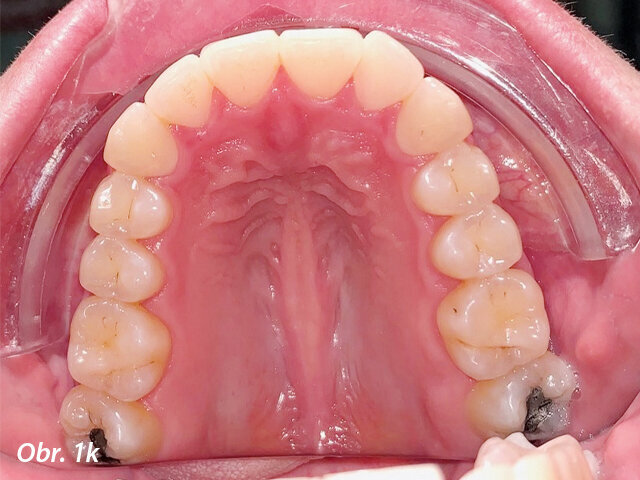

Pacientka 1 – Počáteční fotografie.